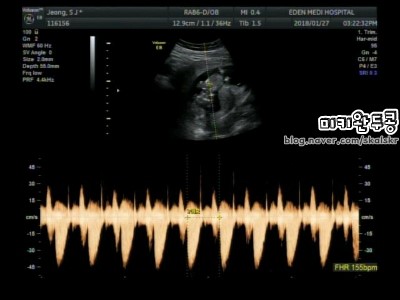

12주 5일_ 2018.1.27 1차 기형아 검사 완료 (NT검사)

12주 5일_ 2018.1.27 1차 기형아 검사 완료 (NT검사) 지난주 토요일 저는 우리 헬롱이의 1차 기형아 검사...